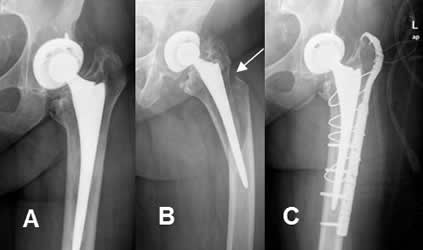

Fig 118. Fractura periprotésica.

Fig 119. Fractura periprotésica.

A: Rx AP. Prótesis en la cabeza femoral.

B: Rx AP. Fractura oblicua y subtrocantérica, con angulación en varo.

C: Rx AP. Fijación de la nueva lesión con placa y cerclaje.